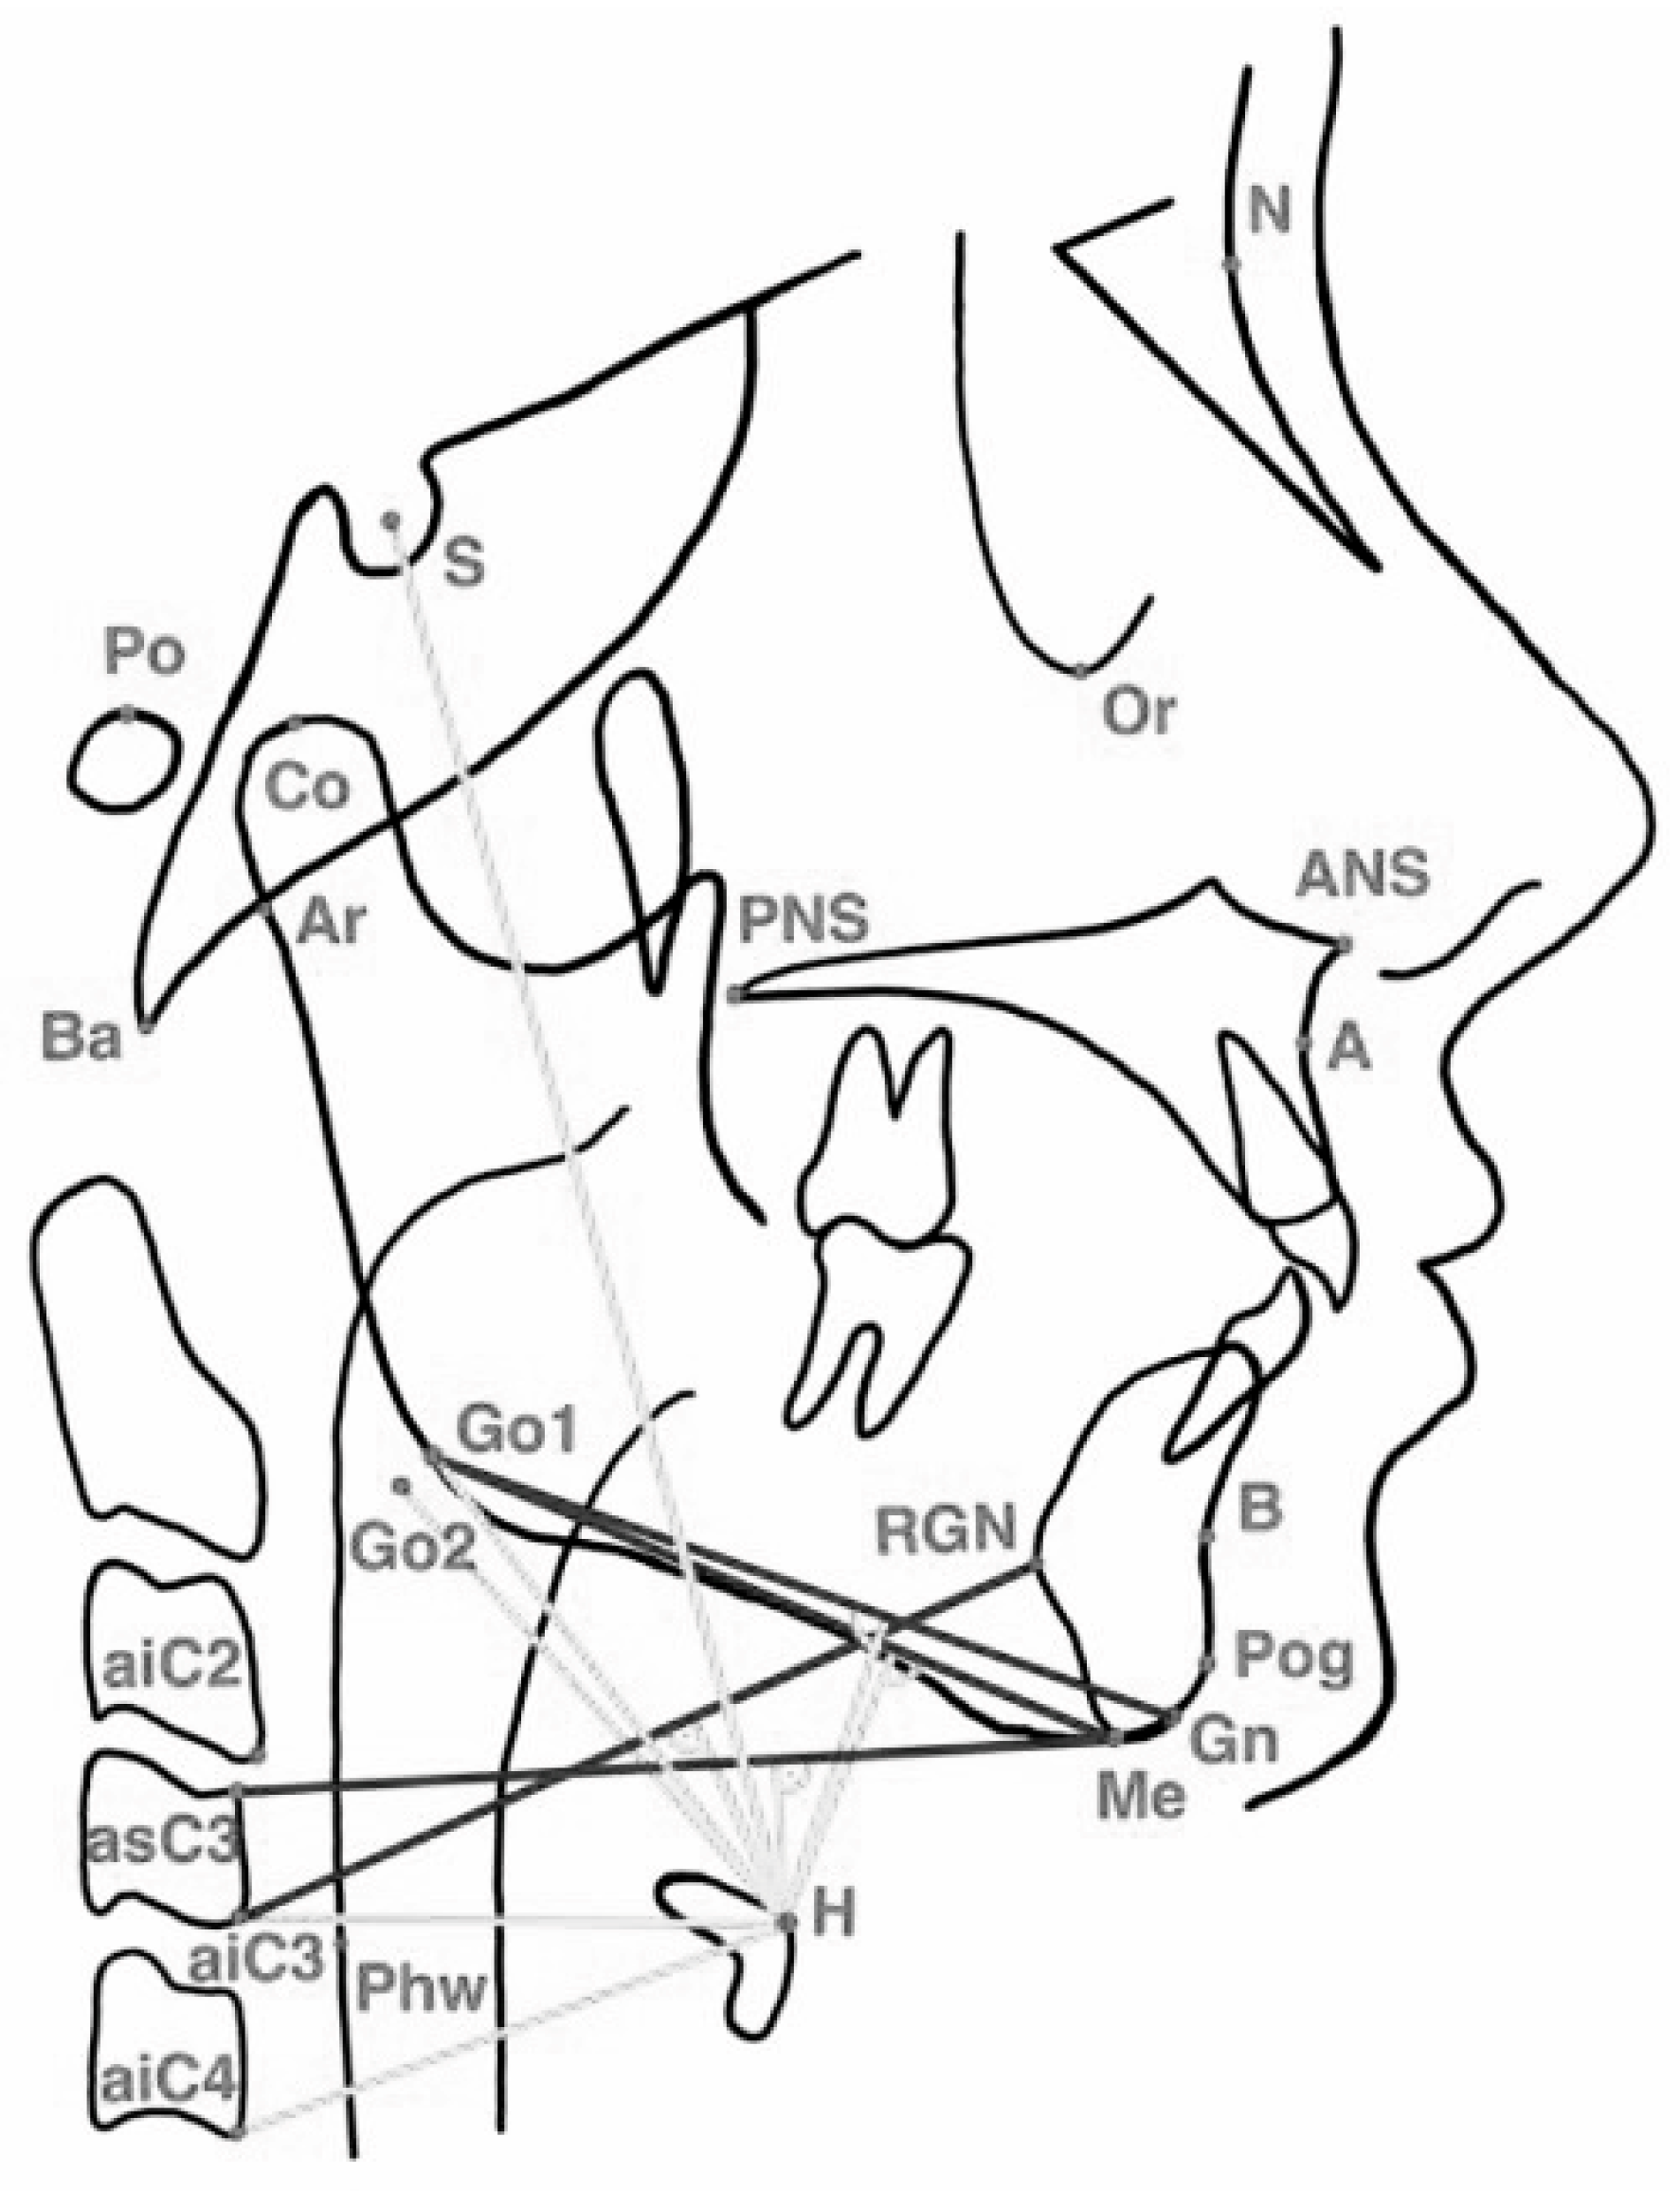

Appendix A. Definitions of Cephalometric Landmarks Used in Hyoid and Craniofacial Analysis

| Acronym | Landmark/Full Term | Definition |

| N | Nasion | The most anterior point of the fron–nasal suture. |

| S | Sella | The midpoint of the sella turcica. |

| Po | Porion | The uppermost point on the external auditory meatus. |

| Or | Orbitale | The lowest point on the inferior margin of the orbit. |

| Co | Condylion | The most superior point on the mandibular condyle. |

| Ar | Articulare | The intersection of the posterior border of the mandibular ramus and the cranial base. |

| Ba | Basion | The most inferior point on the anterior margin of the foramen magnum. |

| ANS | Anterior Nasal Spine | The tip of the anterior nasal spine. |

| PNS | Posterior Nasal Spine | The most posterior point on the hard palate. |

| A | Point A (Subspinale) | The deepest midline point between the anterior nasal spine and the maxillary alveolar crest. |

| B | Point B (Supramentale) | The deepest midline point between the alveolar crest and the chin on the mandibular contour. |

| Pog | Pogonion | The most anterior point on the bony chin. |

| Gn | Gnathion | The most anterior–inferior point on the mandibular symphysis. |

| Me | Menton | The lowest point on the mandibular symphysis. |

| RGN | Retrognathion | The most posterior–inferior point on the bony chin. |

| Go1/Go2 | Gonion (Upper/Lower) | Reference points at the posterior–inferior angle of the mandible used for angular measurements. |

| H | Hyoidale | The most superior and anterior point on the body of the hyoid bone. |

| Phw | Posterior Pharyngeal Wall | The posterior wall of the pharynx at the oropharyngeal level. |

| aiC2, aiC3, aiC4 | Anterior–Inferior Points of Cervical Vertebrae C2–C4 | The most inferior–anterior points of the respective cervical vertebral bodies. |

| asC3 | Anterior–Superior Point of C3 | The most superior–anterior point on the C3 vertebral body. |